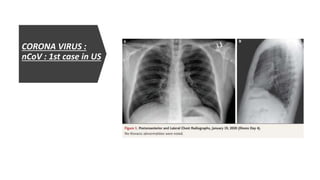

CORONA VIRUS : nCoV : 1st case in US

• December 31st 2019 -----> Clusters of cases of pneumonia in Wuhan,

Hubei Province of -------> Huanan seafood wholesale market -------> On

Jan 7th Chinese authorities confirmed these cases were associated

with novel corona virus.

• First case reported in US was in 20th January 2020.

On January 19, 35-years-old man presented to an urgent care clinic in

Snohomish County, Washington with 4 day h/o cough and subjective

fever

He disclosed he has returned to Washington on January 15 after

traveling to visit family in Wuhan.

He said he had seen the health alert systems from CDC regarding

symptoms of the disease.

On January 20, 2020, the CDC confirmed that the patient’s nasopharyngeal and

oropharyngeal swabs tested positive for 2019-nCoV by real-time reverse-

transcriptase–polymerase-chain-reaction (rRT-PCR) assay.

On admission, the patient reported persistent dry cough and a 2-day history of

nausea and vomiting; he reported that he had no shortness of breath or chest pain.

Vital signs were within normal ranges